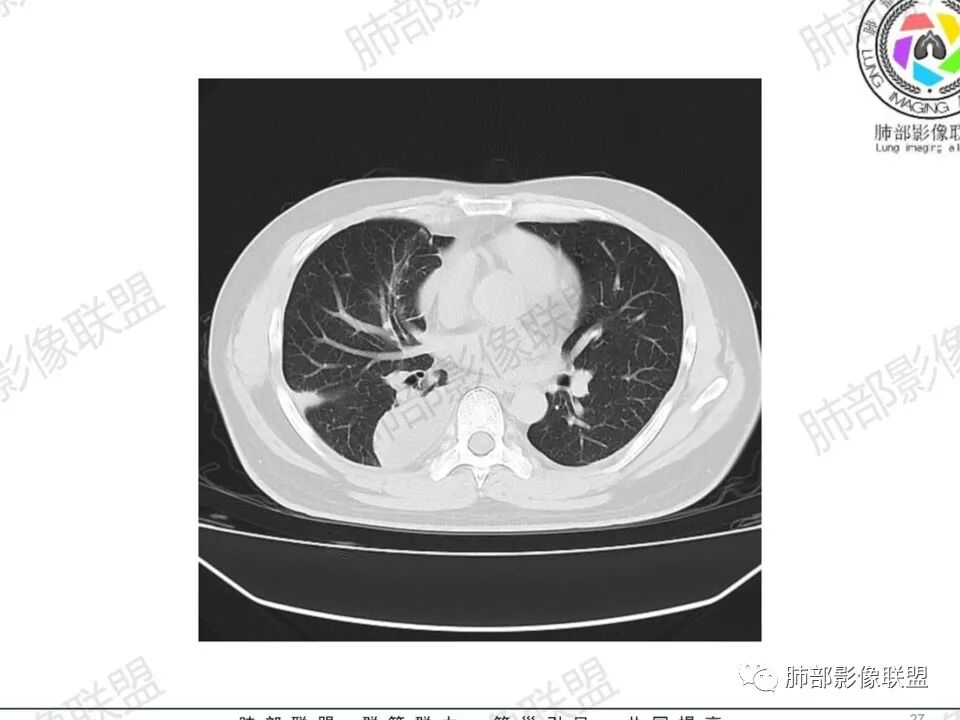

双肺多发结节,胸膜下为主,部分可见空洞。左肺上叶尖后段结节较大,分叶毛刺,周围可见长条索及小斑片影,内空洞比较光滑,内侧壁可见支气管通过。右肺下叶后基底段不张实变,后侧积液,右侧水平裂积液,右侧膈胸膜纵膈胸膜增厚积液,右侧侧胸膜肥厚,考虑1:一元金葡。2二元:金葡,左肺上叶结核。

男,45岁,左手指红肿疼痛两天,右侧胸壁疼痛伴发热12小时入院。患者急性起病,胸部CT示双肺多发结节,部分伴空洞,空洞壁较光滑,右侧胸腔积液,考虑感染性病变,金葡菌加SPE可能

尘缘: @赵永兵 内蒙巴市临河妇幼影像科 左上肺也是胸膜下(胸膜顶下)的SPE。

@赵永兵 内蒙巴市临河妇幼影像科 支气管是从旁边经过,所以不是空洞,是胸膜下的脓毒栓。如果是结核空洞,应该与支气管相通(因为结核没有血播感染表现的时候,来源是气道,空洞应该与支气管相通),所以支气管从旁边经过,这病灶又在胸膜下,周围也没有干酪坏死。当然是SPE了。

中年男性,左手中指及胸壁疼痛伴发热来诊,影像见双肺多发结节,胸膜下分布为主,部分结节可见空洞,边缘模糊。左肺上叶尖后段结节较大。右肺下叶后基底段不张实变,右侧叶间裂及右侧胸腔积液,右侧侧胸膜肥厚。考虑金葡菌感染,血播SPE。